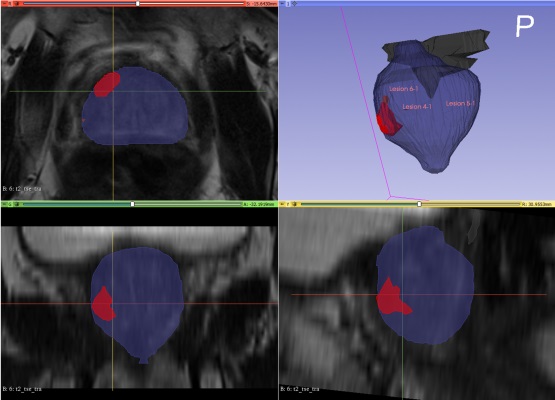

Технология Prostate Intelligence компании Lucida Medical использует радиогеномику*, машинное обучение и обработку изображений для анализа снимков МРТ. Результаты испытаний показывают, что она может помочь автоматизировать трудоемкие задачи, такие как выделение очагов поражения, и избежать ненужных инвазивных биопсий, работая с беспрецедентной точностью и последовательностью.

В настоящее время МРТ является предпочтительной методикой для оценки целого ряда онкологических заболеваний, включая рак предстательной железы и метастатические заболевания. Однако нынешний процесс интерпретации радиологами онкологической МРТ требует специальной подготовки и является трудоемким, что создает растущую проблему с квалификацией. При этом, как показало исследование PROMIS, радиологи могут пропустить 12% значительных раковых образований на МРТ, что приводит к тому, что 55% людей без значительного рака подвергаются болезненной и дорогостоящей биопсии. Исследование, представленное на ECR 2021, предполагает, что технология искусственного интеллекта Lucida Medical может помочь сократить количество пропущенных раковых опухолей до 7% и ненужных биопсий до 24%, а также ускорить процесс.